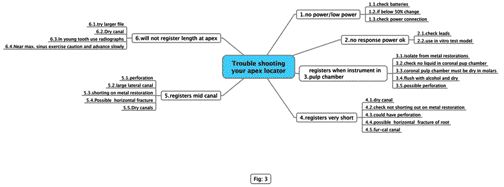

Tale of Two Specialties: The Endodontic/Implant Algorithm

Change is a significant evolutionary tool provided it rests upon a solid and secure foundation. Innovations in materials and technologies occurring within the dental field are impacting powerfully on its art and science; however, dentistry, like all health care, is both a business and a profession. The pendulum swings that predicate trends and transitions within … Read more